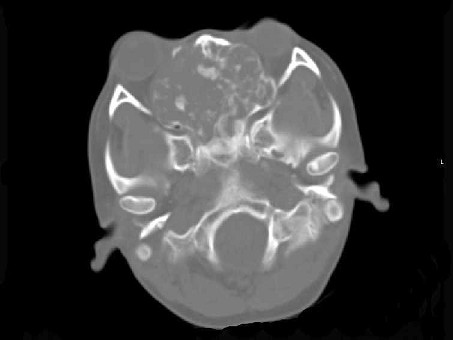

[多选题]男,28岁,因鼻塞、头痛1年余,鼻窦CT扫描如图所示,正确的描述或诊断是()A.双侧上颌窦、筛窦、鼻腔及蝶窦内见软组织肿块影B.肿块内密度不均,有较多

A.双侧上颌窦、筛窦、鼻腔及蝶窦内见软组织肿块影

B.肿块内密度不均,有较多致密钙化影

C.窦壁及颅底骨质破坏